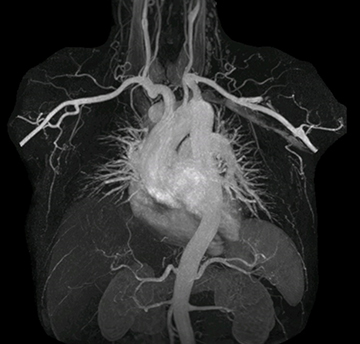

The subtractionless peripheral MR angiography shows improved vessel-to-background contrast and high resolution. Ingenia Ambition 1.5T.

“Before we had Ingenia Ambition, our CE-MRA run-off studies would first acquire a dynamic pre-contrast scan with 20-25-second breath-holds, then inject the contrast, do another acquisition and then subtract the two,” says Avila. “Now, mDIXON XD allows us to complete the study in just one single pass – without need for a pre-exam – which eliminates subtraction artifacts and almost halves the scan time. In addition, mDIXON provides much better background suppression, which really improves vesselto-background contrast. And, thanks to Compressed SENSE, the single breath-hold is not long and we improve image resolution.”

The time saved by Compressed SENSE and mDIXON XD is sometimes used to include additional sequences. An example are peripheral MRA studies, in which Compressed SENSE and mDIXON XD help achieve a 5- to 10-minute reduction in scanning time. This brings the total time down, from the 45 minutes needed with their previous system to about 30 to 35 minutes on Ingenia Ambition, thus providing ample time to include additional sequences.